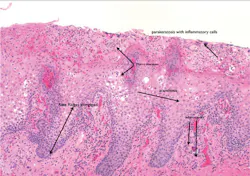

Histology: The rete ridges exhibit hyperplasia and inflammation in the lamina propria. Fissuring is often exhibited along with the characteristics of geographic tongue. There is loss of the keratin hairs on the filiform papillae with prominence of the fungiform papillae. Geographic tongue is characterized with microabscesses in the upper epithelial layers (see Figure 3).